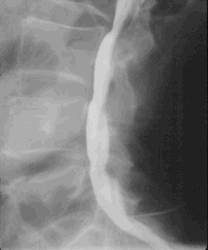

Myelographie

Bei der Myelographie wird ein Kontrastmittel in den Wirbelkanal gespritzt und davon eine Röntgenaufnahme gemacht um Bandscheibenvorfälle und andere Raumforderungen im Wirbelkanal nachzuweisen.